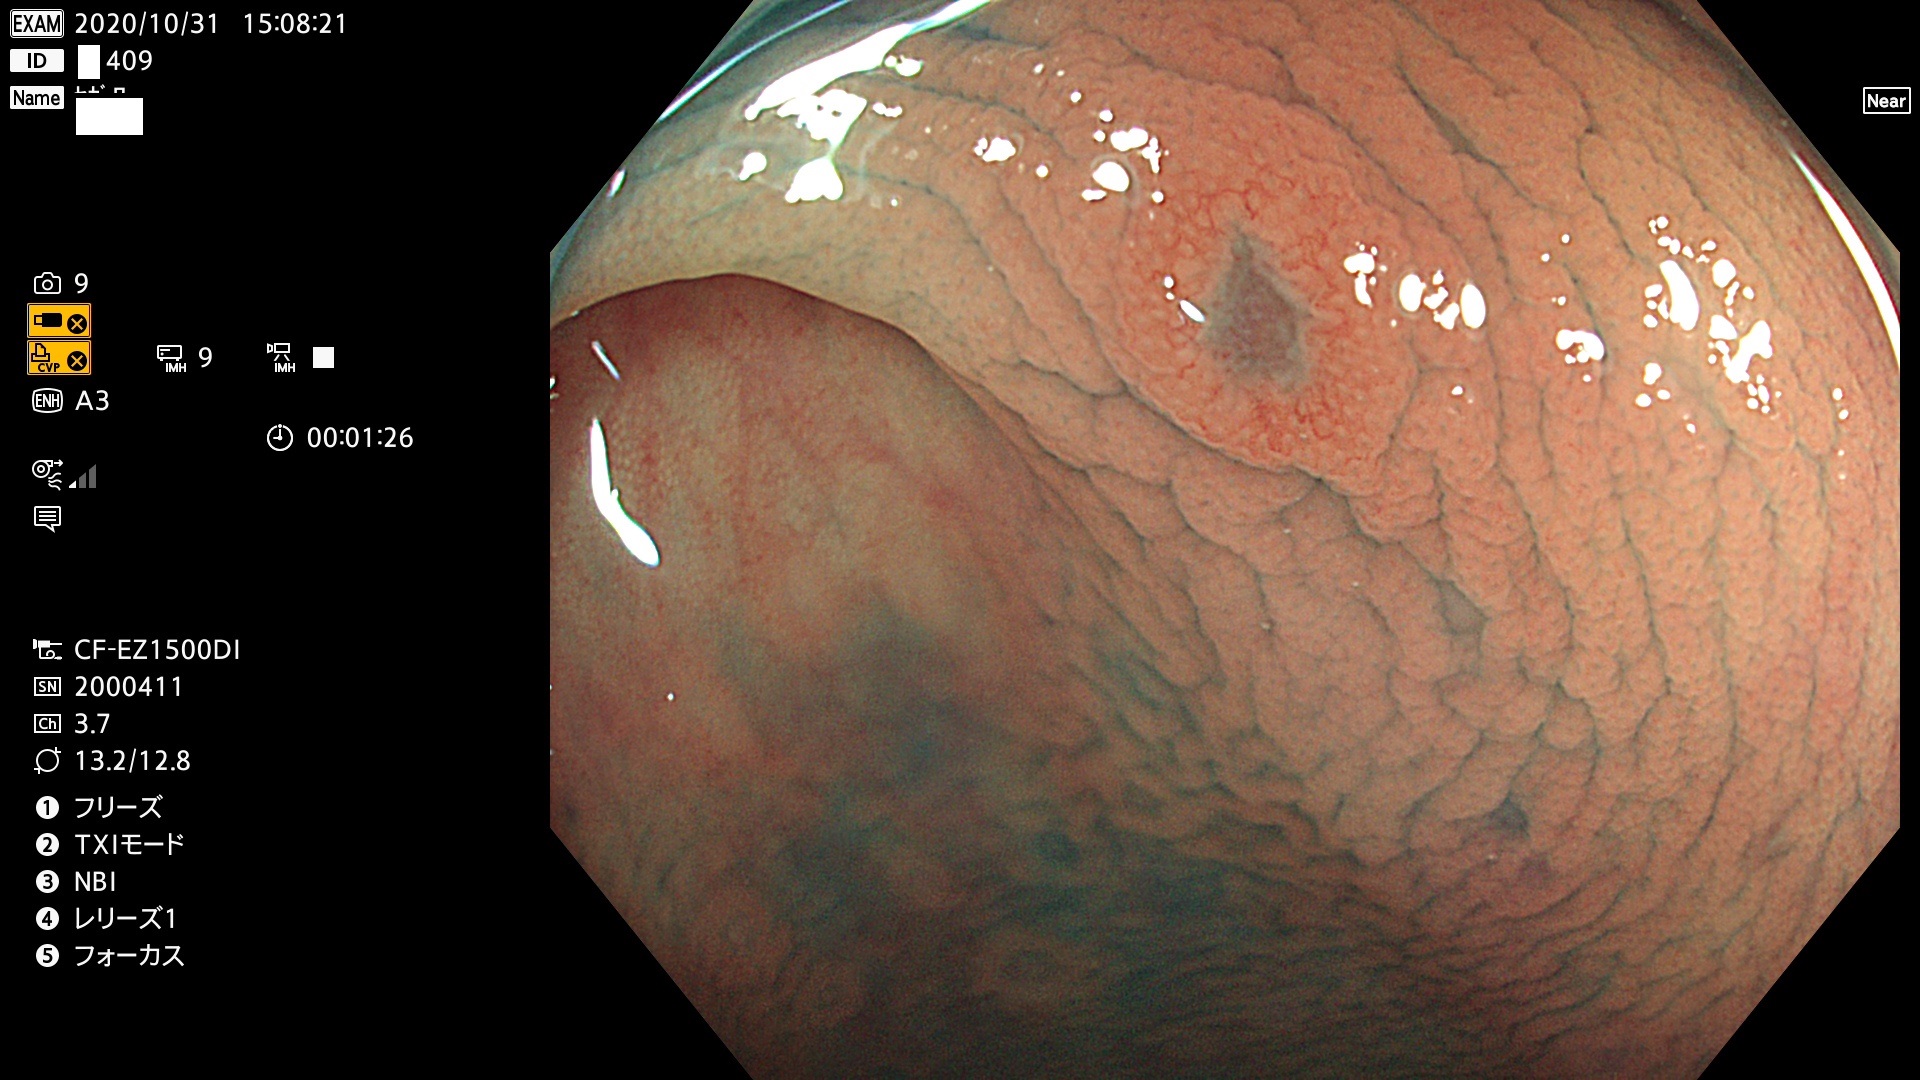

以下は当院で経験した「ビランと鑑別の難しいUc型腺腫」です(全て、病理で腺腫を確認済み)。

このような病変は表面を拡大観察しても診断は不可能であり、現在の内視鏡診断の「限界を超えた病変」と言えます。現実的な対策は「典型的なビランと異なる」と感じたら、「コールド法で積極的に切除する」ことと考えます。もちろん「結局はビランだった(不要な過剰切除だった)」ということもあります。しかしコールド法なら重篤な合併症は稀であり、医師は切除を躊躇すべきではないと考えます。